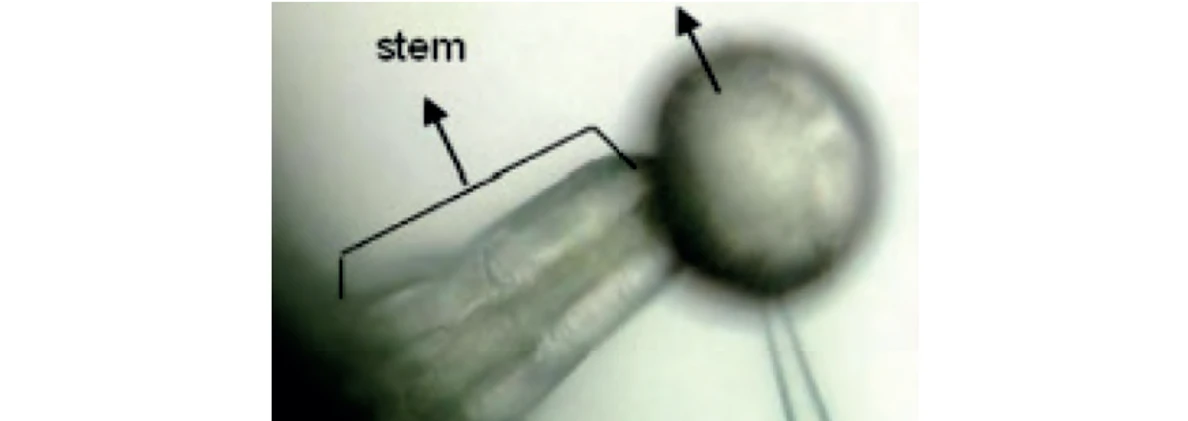

Těla rostlin konopí jsou pokryta trichomy (Obr. 1). Trichomy se dělí do 2 kategorií: nežláznaté a žláznaté. Mezi žláznaté trichomy patří baňaté, stonkové přirostlé a stonkové kulovité. Stonkové kulovité trichomy (Obr. 2) jsou tvořeny hlavičkou a stonkem. Hlavička obsahuje diskovité buňky, které jsou obklopeny skladovací dutinou. Předpokládá se, že diskovité buňky jsou místem produkce kanabinoidů. Happyna a spol. (11) použili ke studiu distribuce a hustoty trichomů rostlin C. sativa skenovací elektronovou mikroskopii (SEM). Pomocí SEM bylo zjištěno velké množství stonkových přirostlých trichomů pouze na květech v průběhu kvetení a s vysokou hustotou výskytu zejména na listenech a okvětních lístcích. Pomocí kapalinové chromatografie s hmotnostní detekcí bylo ověřeno, že přítomnost těchto trichomů je zodpovědná za výskyt kanabinoidů v květu. Dále analýza odhalila přítomnost vláskovitých přirostlých kulovitých trichomů na květech, stoncích a listech ve vegetativní i rozmnožovací fázi rostliny. Stonkové přirostlé trichomy (Obr. 3) mohou být rozděleny podle velikosti: velké nacházející se pouze na květech a malé vyskytující se na květech, listech a stoncích. Baňaté trichomy (Obr. 4), mající tvar balonu, jsou nejmenšími trichomy, které je možné najít na povrchu rostliny. Obvykle jsou tvořeny dvěma maximálně čtyřmi buňkami (11).

PČR: Obr. 2 – Stonkový kulovitý trichom tvořený hlavičkou a stonkem (11)

PČR: Obr. 2 – Stonkový kulovitý trichom tvořený hlavičkou a stonkem (11)